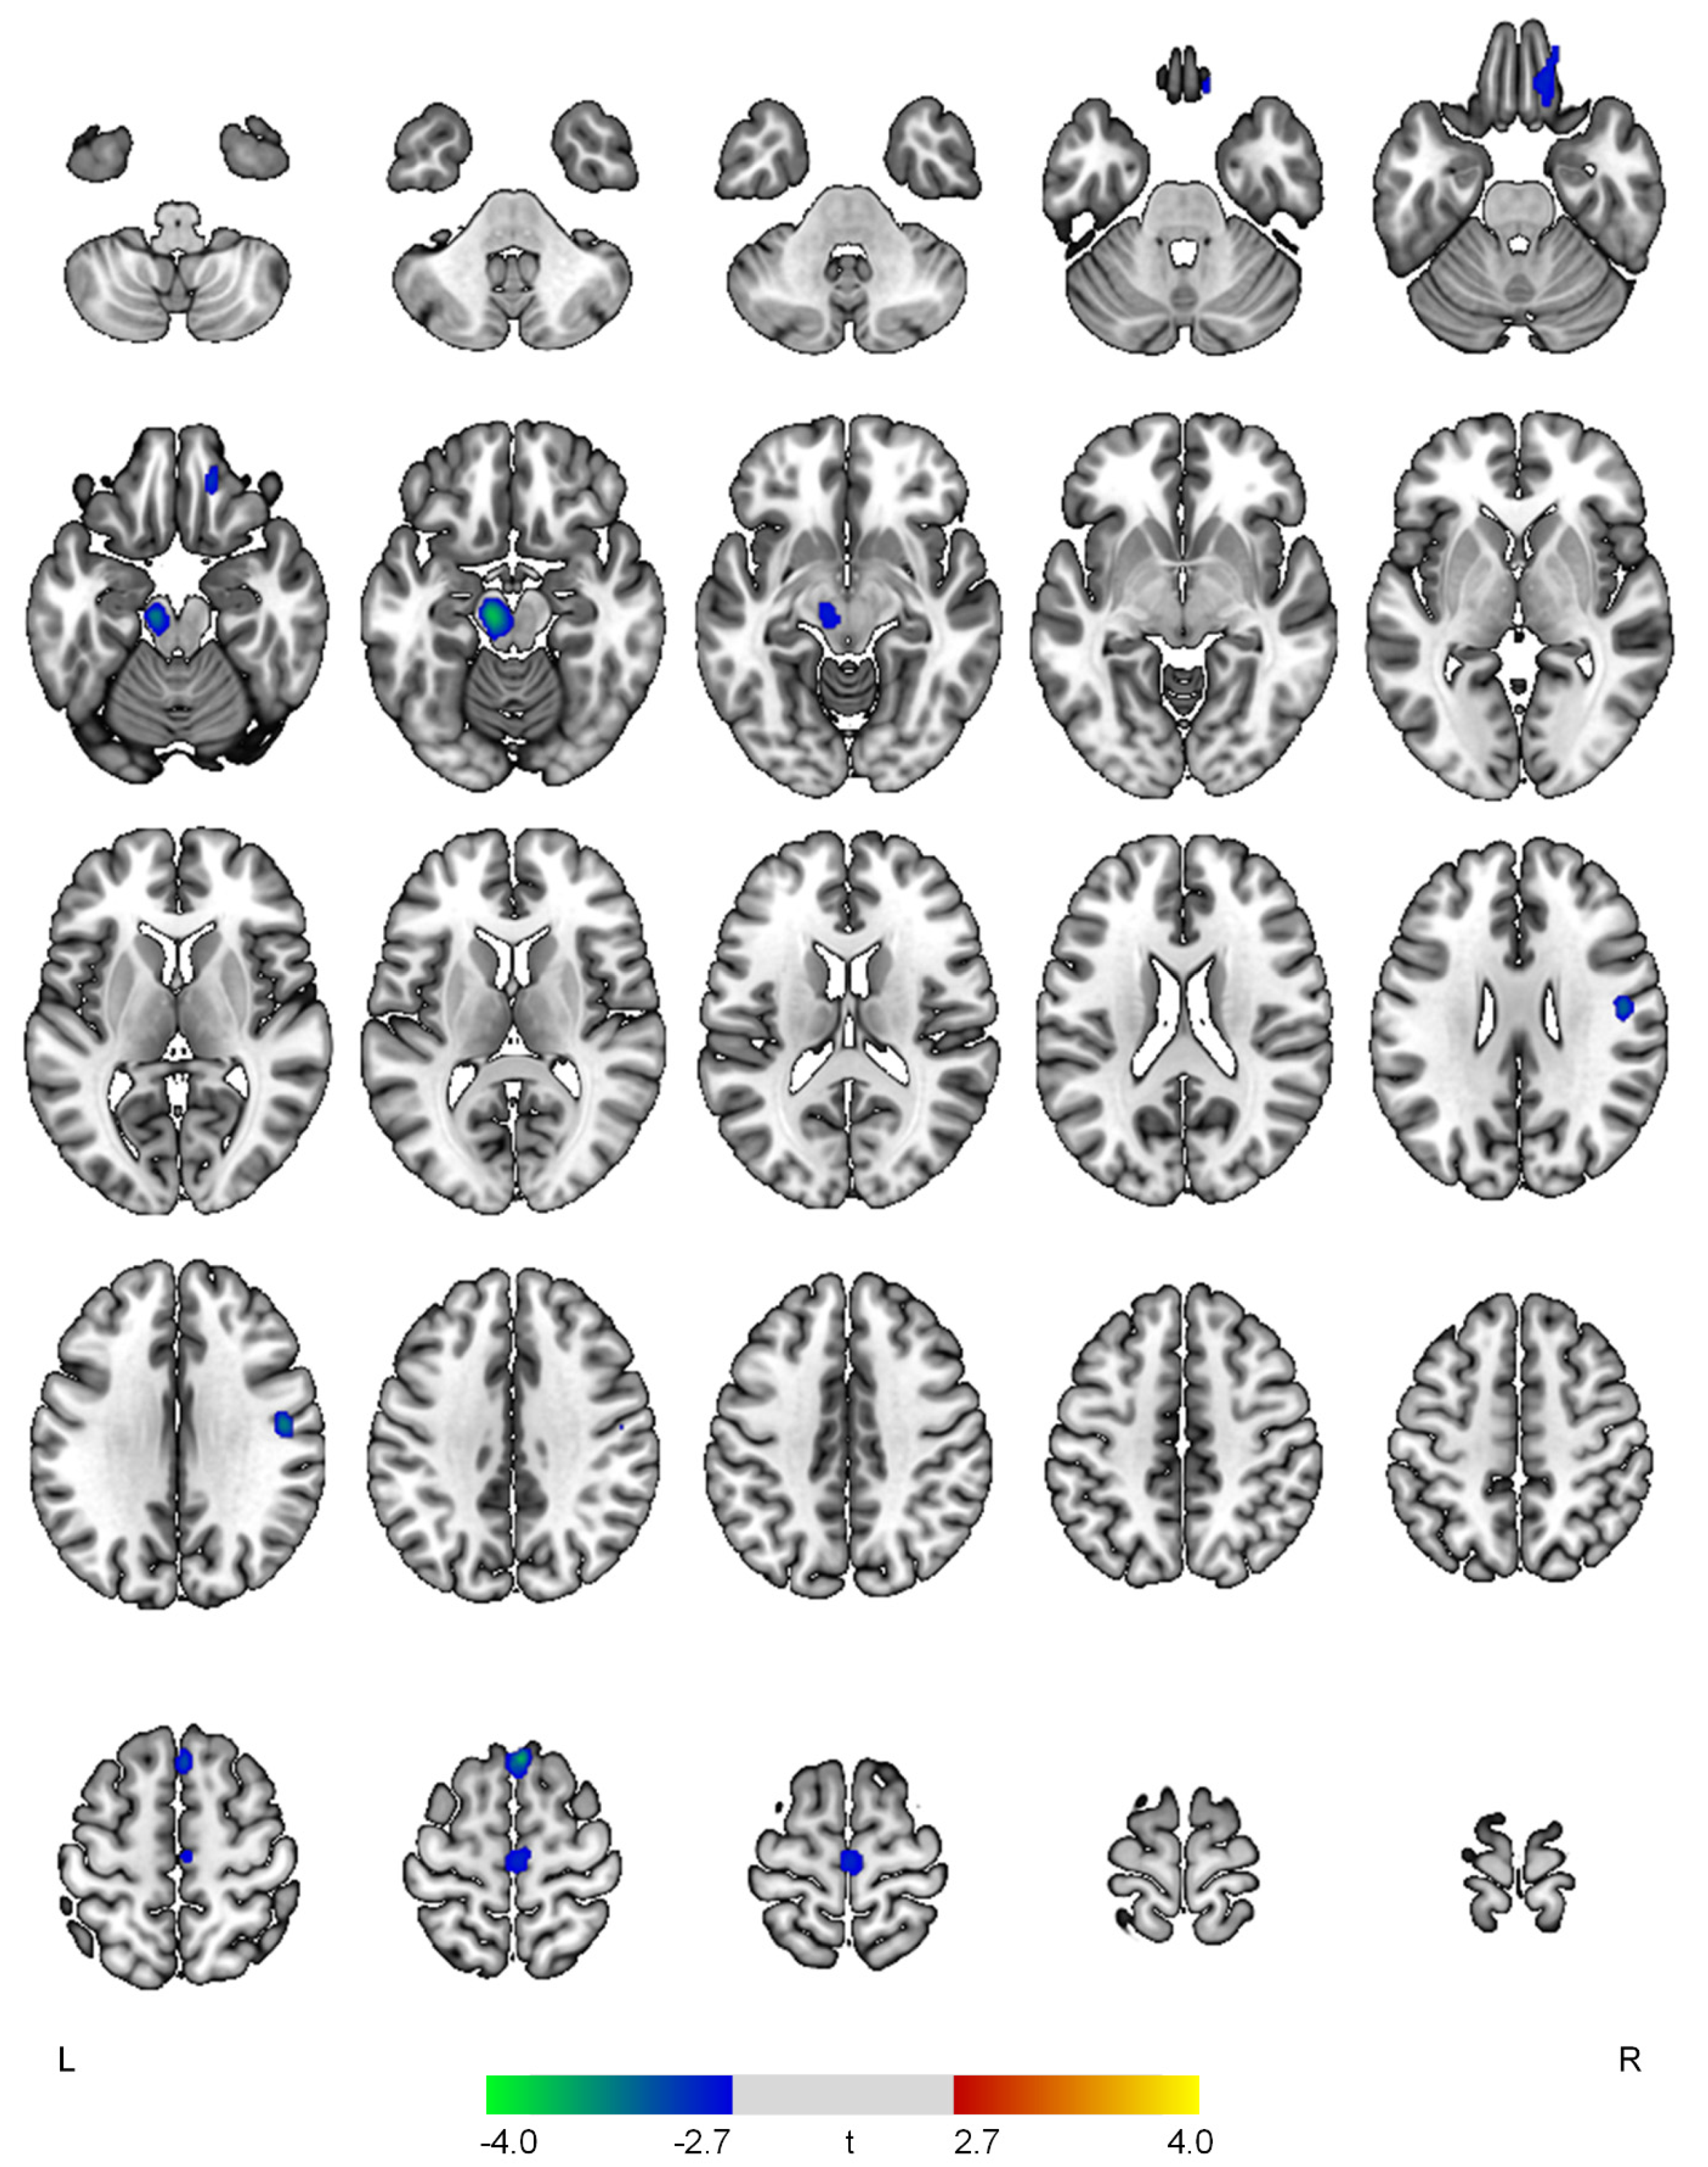

| None | ||||

| Negative correlations with the apathy domain | ||||

| R superior frontal gyrus | 3.74 | <0.001 | 138 | 4, 26, 64 |

| L midbrain | 3.69 | <0.001 | 265 | −10, −20, −16 |

| R postcentral gyrus | 3.33 | 0.001 | 111 | 48, −10, 30 |

| R medial orbital gyrus | 3.01 | 0.002 | 177 | 16, 40, −22 |

| R precentral gyrus | 2.89 | 0.003 | 156 | 2, −20, 64 |